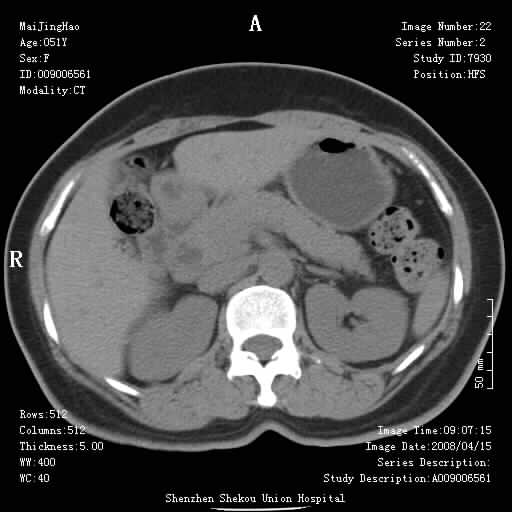

以下是引用余辉在2008-4-26 8:55:00的发言:[br]患者有结石史,此次腹痛4小时,胆总管全程扩张,应有胆总管末端梗阻,此次仍考虑胆结石症,积气不外两种原因,一种是结石下移时肠道内气体逸入,其次为产气菌感染。(倒数第三幅图像于扩张之胆总管末端似可见稍高密度影,考虑为结石影)

以下是引用听蝉观竹在2008-4-26 11:41:00的发言:[br]胆道手术分两种情况:[br]1、如果仅仅做胆囊切除手术,肝内胆管不会积气,只会出现胆总管代偿扩张,因为奥迪氏括约肌依然功能正常胆道与外界并不相通;[br][br]2、胆囊切除+胆总管空肠吻合手术(即roux-y式),则肝内胆管会出现积气,只是因为胆管与小肠相通,气体来源于小肠。这是临床十分常见的手术。[br][br]这个病例应该是胆囊切除+胆总管空肠吻合手术,是正常手术后表现,并不是胆道感染的表现。